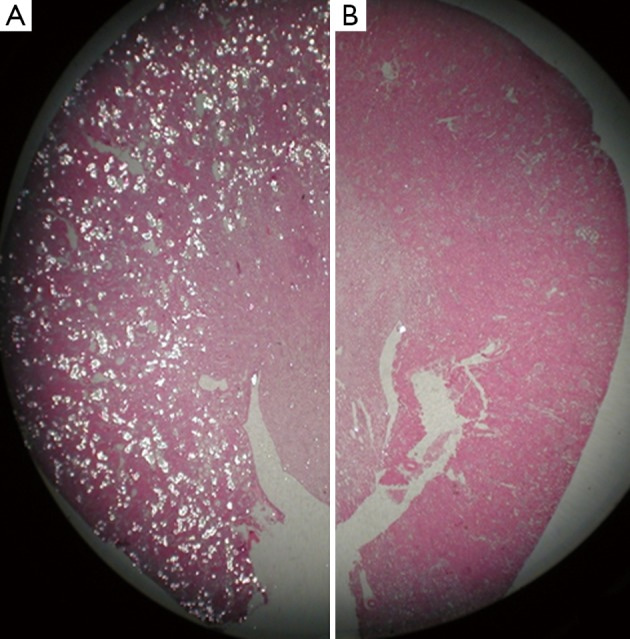

In animal models of calcium oxalate nephrolithiasis and hyperoxaluria, the treatment with vitamin E improved tissue levels of antioxidant enzymes, reduced injury and eliminated calcium oxalate crystal deposition in the kidneys [Thamilselvan 2005]. The administration of an antioxidant apocynin nearly completely reversed the effects of hyperoxaluria in animal models and reduced the deposition of calcium oxalate crystals in kidneys as a proof-of-concept (Figure 8) [Khan 2014]. Functional assays of this nature can be replicated with clinical samples of epithelial and endothelial cell types obtained from renal stone formers, with exposure to calcium oxalate crystals on a microfluidic platform alongside pathological shear, to observe therapeutic effects of small molecule antioxidant drugs.

Figure 8: Experimental outcomes of hematoxylin and eosin-stained paraffin sections of a kidney obtained from a hyperoxaluric rat model. Tissue sections were examined under light microscopy to indicate; A) a hyperoxaluric rat with renal tubules full of birefringent calcium oxalate crystals, b) hyperoxaluric rat receiving an antioxidant apocynin showed only the presence of a few birefringent crystals of calcium oxalate. Credit: [Khan 2014].